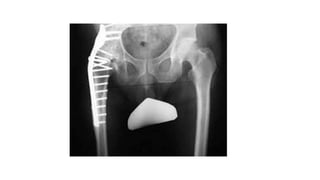

Radiographic examinations of the

joints are essential, both weight bearing

and non-weight bearing to know the

status of the joints (subluxation or

dislocation, stability of the joints )